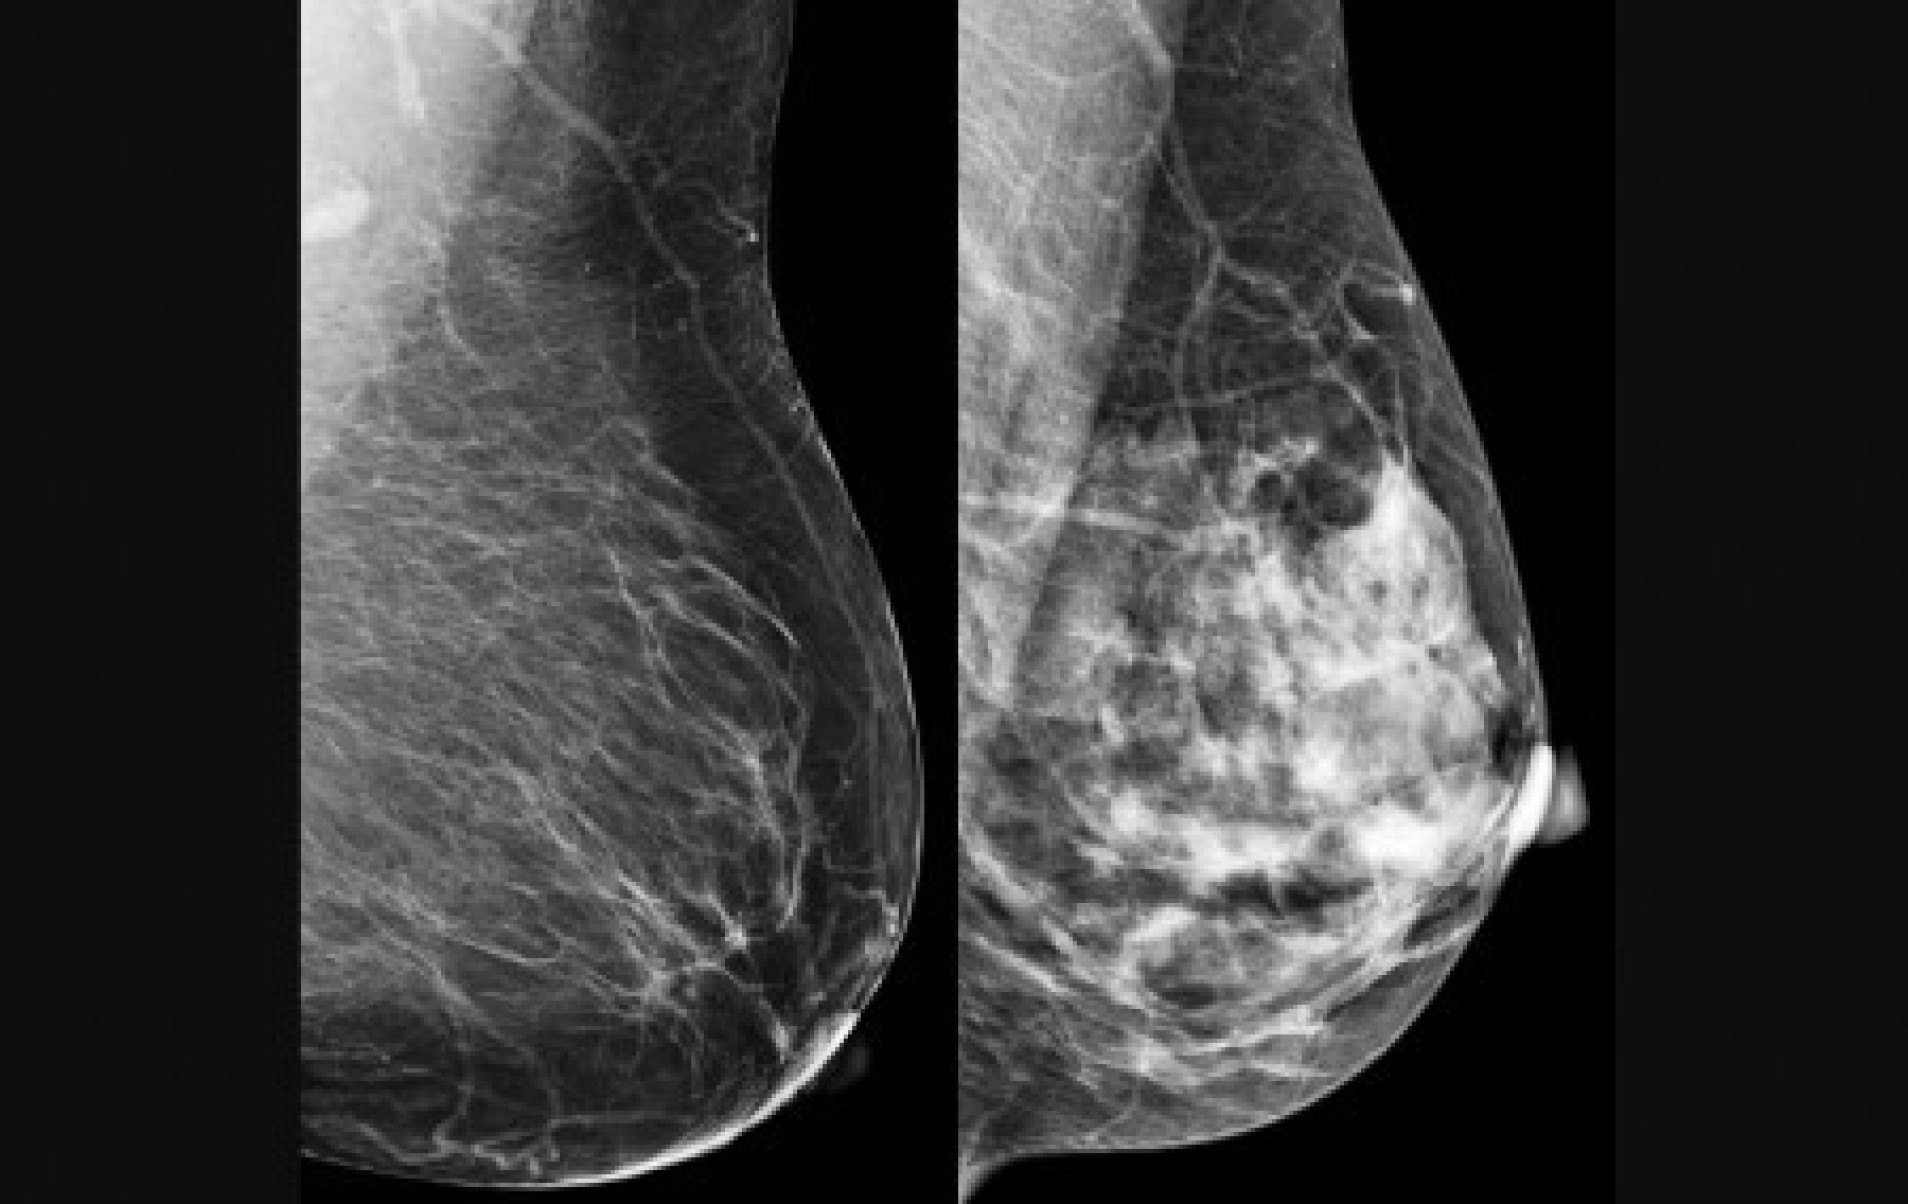

O câncer de mama foi escolhido como alvo para teste do modelo computacional porque é o tipo mais comum entre mulheres no mundo, com 2,3 milhões de casos e 670 mil mortes registradas em 2022. A detecção precoce é crucial para aumentar as chances de cura e sobrevida. No entanto, métodos tradicionais, como a mamografia, dependem fortemente da interpretação humana, o que pode levar a variações no diagnóstico. “Apesar de ser teoricamente simples de acompanhar, a mamografia ainda é um exame cuja interpretação depende muito do profissional que realiza o procedimento”, diz Papa.

No estudo, as informações codificadas nos qubits foram pixels das imagens de mamografia e ultrassonografia. Às vezes, um pixel apenas; às vezes, mais de um. O modelo foi testado com duas bases de dados: BreastMNIST (com imagens de ultrassonografia) e BCDR (com mamografias segmentadas). Mesmo utilizando um circuito com apenas quatro qubits, a rede híbrida obteve desempenho competitivo. No melhor caso, alcançou 87,2% de acurácia no conjunto de teste e 86,1% no de validação. “A ideia foi criar uma arquitetura que poderá ser utilizada e aprofundada em outros estudos”, comenta Rodrigues.